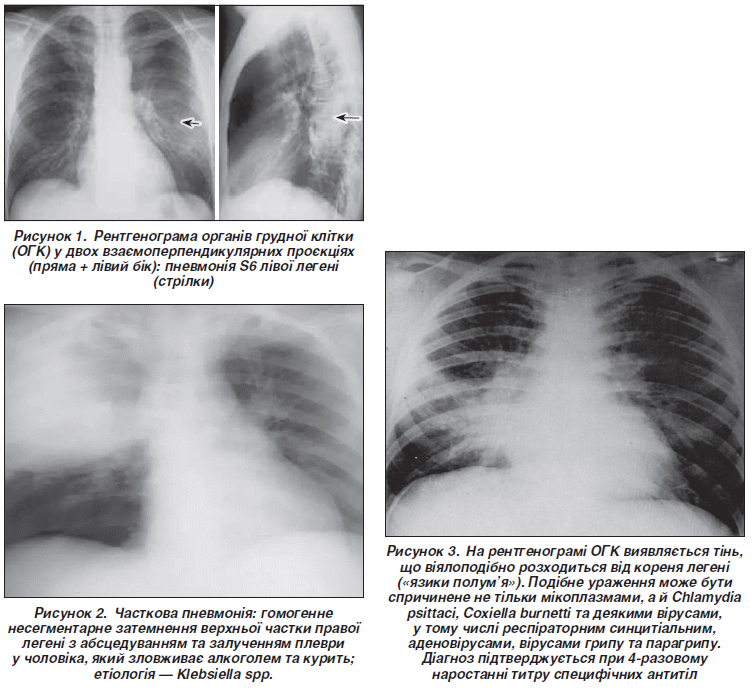

У цьому диференційно-діагностичному полі мають значення особливості клінічної картини пневмонії, які характерні для різних етіологічних патогенів. Так, пневмококова позалікарняна пневмонія характеризується гострим початком, високою лихоманкою, болями у грудях, кашлем. Лихоманка може бути двофазною. Зазвичай ідентифікувати збудника не вдається, оскільки неінвазивні дослідження (аналіз мокротиння) неінформативні та виконуються із запізненням. Для пневмокока рентгенологічна картина характеризується гомогенним несегментарним затемненням із залученням плеври та нечіткими межами, альвеолярною та/або частковою інфільтрацією, а також фокальним неоднорідним затемненням з нечіткими межами, що має сегментарну конфігурацію і бронхопневмонічні інфільтрати (рис. 1) [7].

Пневмонія, викликана клебсієлою, має більш тяжкий перебіг. Виникає в ослаблених, з супутньою патологією хворих та алкоголіків. Аускультативна картина мізерна. Перебіг стрімкий, може ускладнитися абсцесом і гангреною легені. Мокрота кольору чорносмородинового желе. Висока смертність. Klebsiella spp., Proteus spp., пневмококи є типовими патогенами так званої часткової пневмонії, хоча подібну клініко-рентгенологічну картину викликають також мікоплазми та Legionella spp. За даними рентгенографії візуалізується гомогенне несегментарне затемнення із залученням плеври, що свідчить про первинне ураження дистальних відділів дихальних шляхів. Є симптом «повітряної бронхограми», обсяг легеневої тканини, як правило, не змінюється (рис. 2) [8].

Мікоплазмовий процес у паренхімі легені характеризує ПП з поступовим початком і частіше зустрічається у дітей, підлітків та осіб віком до 30 років. Інфекція передається повітряно-краплинним шляхом, інкубаційний період триває 10–20 днів. Часто захворювання поширене в організованих колективах, має епідемічний характер ураження, виражену інтоксикацію. За даними рентгенограми та КТ ОГК спочатку відзначається інтерстиціальна інфільтрація, а потім з’являються сегментарні або часткові ацинарні (центролобулярні) інфільтрати (на КТ це затемнення у вигляді «матового скла»), прикоренева інтерстиціальна інфільтрація. Іноді виявляють скупчення ексудату в плевральних порожнинах та/або лімфаденопатію (особливо у дітей) [9]. Рентгенологічні ознаки з’являються пізніше, ніж клінічні, і полягають у великих сегментарних або часткових інфільтратах, які резорбуються (розсмоктуються) протягом тривалого часу (рис. 3).

Слід зазначити, що за рентгенологічними даними визначити етіологію пневмонії надзвичайно складно. Однак у цьому може і не бути потреби, оскільки клінічна картина разом із результатами дослідження дозволяє розпочати лікування антибіотиками емпірично згідно з 4 клінічними групами ПП. У найкращому випадку можна відрізнити вірусну пневмонію від бактеріальної. Частковою консолідацією в типових випадках характеризуються пневмококи, Klebsiella spp., Legionella spp. та Mycoplasma spp. Віруси та мікоплазма викликають інтерстиціальну та змішану інтерстиціально-альвеолярну інфільтрацію (рис. 5), а Haemophilus influenzaе та стафілококи — бронхолегеневу інфільтрацію.